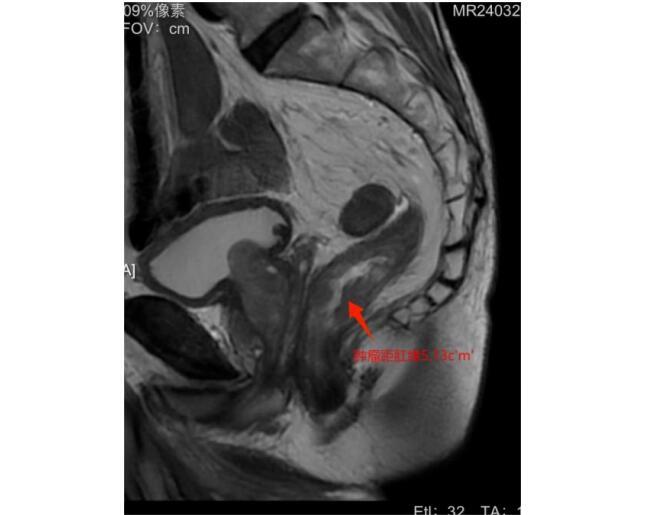

今年84岁的陈奶奶(化名)在两周前因“排便次数增多且伴有暗红色血液”来到哈医大四院胃结直肠外科门诊,找到了陈洪生教授就诊。通过丰富的经验结合肛门指检,陈洪生教授准确地识别出老人家可能患有直肠的肿瘤且位置很低。入院后,通过肠镜及直肠核磁评估,诊断为低位直肠癌,肿瘤距肛缘5cm,评估pT3N1M0。

81岁的周老(化名)因间断便血,肠镜检查发现直肠恶性肿瘤,肠镜及直肠核磁评估肿瘤距肛缘5cm,肿瘤的位置同样很低,患者及家属为求保肛手术治疗,慕名找到陈洪生教授。通过细致的术前评估和术前准备,在克服了男性骨盆狭窄等不利条件下,经过艰苦的努力,陈洪生教授团队再次成功实施了“腹腔镜完全经腹入路直肠括约肌间切除术(ISR)”,既切除了直肠的恶性肿瘤,又极限地保留了肛门和肛门的功能。